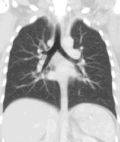

A CT scan can be used for detecting both acute and chronic changes in the lung parenchyma, the tissue of the lungs.[66] It is particularly relevant here because normal two-dimensional X-rays do not show such defects. A variety of techniques are used, depending on the suspected abnormality. For evaluation of chronic interstitial processes such as emphysema, and fibrosis,[67] thin sections with high spatial frequency reconstructions are used; often scans are performed both on inspiration and expiration. This special technique is called high resolution CT that produces a sampling of the lung, and not continuous images.[68]

Vascular Imaging

Computed tomography angiography (CTA) is a type of contrast CT to visualize the arteries and veins throughout the body.[111] This ranges from arteries serving the brain to those bringing blood to the lungs, kidneys, arms and legs. An example of this type of exam is CT pulmonary angiogram (CTPA) used to diagnose pulmonary embolism (PE). It employs computed tomography and an iodine-based contrast agent to obtain an image of the pulmonary arteries.[112][113]